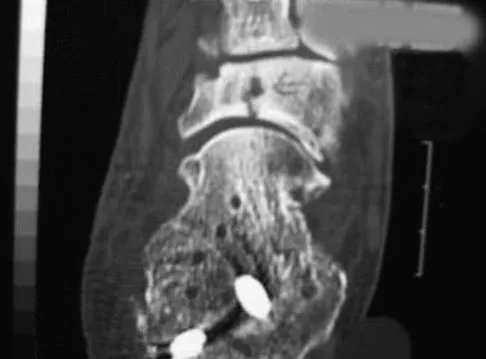

A 28-year-old man has had a 2-year history of progressive lateral ankle pain. History reveals that he underwent a triple arthrodesis at age 13 for a tarsal coalition. The pain has been refractory to braces, custom inserts, and nonsteroidal anti-inflammatory drugs. Weight-bearing radiographs of the ankle and foot are shown in Figures 3a through 3d. Surgical management should include which of the following?

Explanation